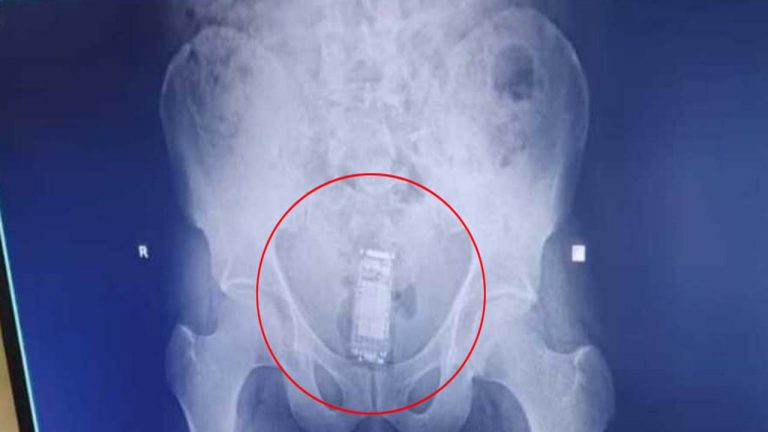

Gujarat: కంత్రీ ఖైదీ.. మొబైల్ ఎక్కడ దాచాడో తెలిస్తే షాక్ అవ్వాల్సిందే!

జైలు అంటే కట్టుదిట్టమైన భద్రత. నిరంతరం పర్యవేక్షణ ఉంటుంది. బయట వారిని లోపలికి పంపించరు. చాలా పగడ్బందీగా జైలు పరిసరాలు ఉంటాయి. అలాంటిది ఓ ఖైదీ దగ్గర మొబైల్ ఉండడాన్ని చూసి షాక్ అయ్యారు.